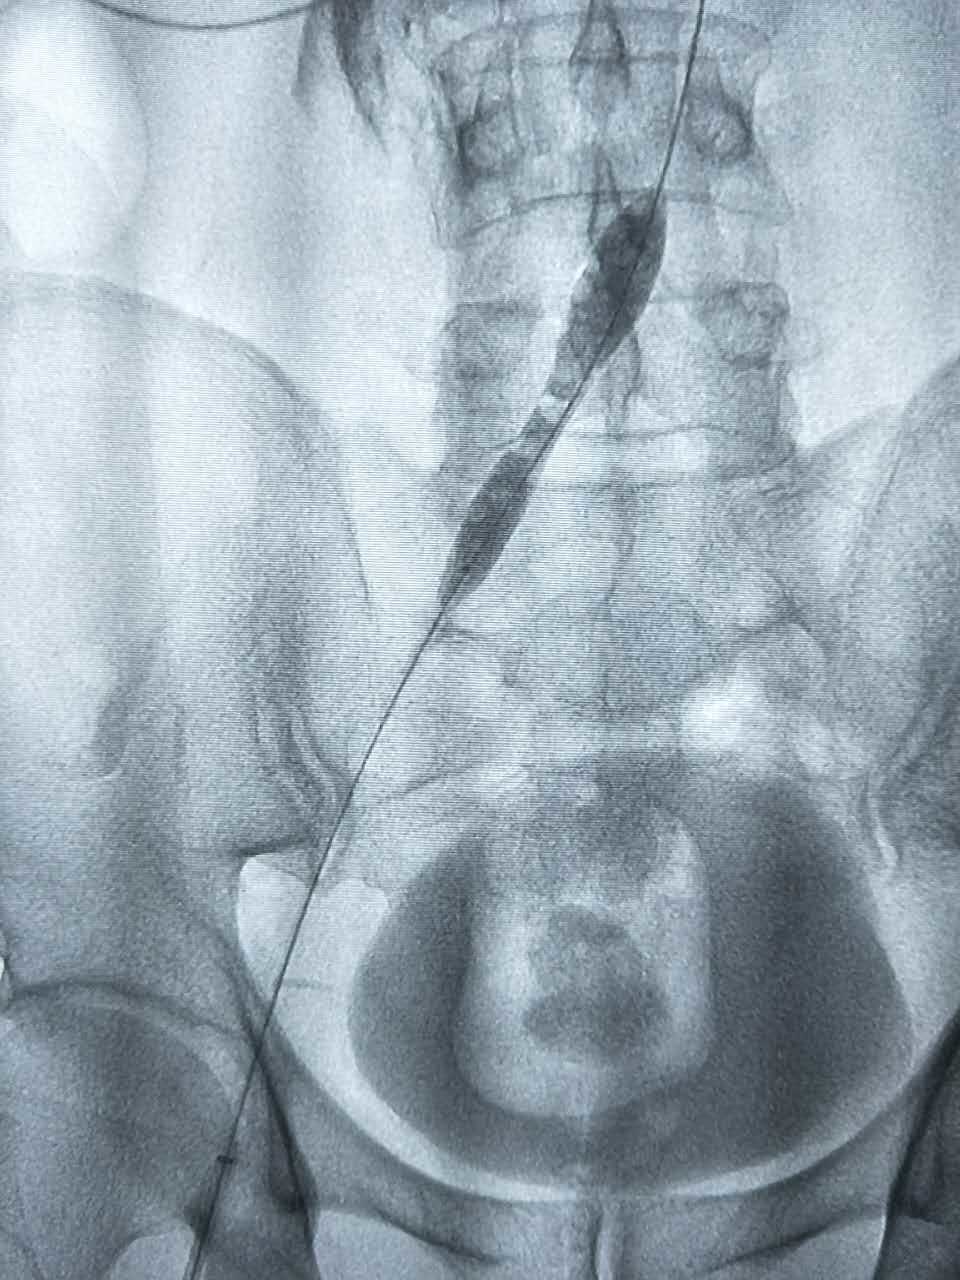

腿肿的原因分析

960x1280 - 152KB - JPEG